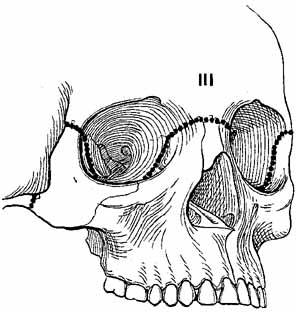

The LeFort III fracture (craniofacial dysjunction) is a disarticulation of the facial skeleton from the base of the skull (Fig. 15). The fracture extends from the nasofrontal suture to the medial orbital wall at the level of the cribriform plate, along the orbital floor, following the inferior border of the greater wing of the sphenoid, and across the lateral wall, through the zygomatic arch and pterygoid plates. Because of the more posterior extent of this fracture, structures in the optic foramen and superior orbital fissure are highly susceptible to injury.

Fig. 15 LeFort III fracture. (From Iliff NT: The ophthalmic implications of the correction of late enophthalmos following severe midfacial trauma. Trans Am Ophthalmol Soc 89:477–548, 1991)